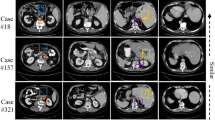

Few-shot segmentation (FSS) models have gained popularity in medical imaging analysis due to their ability to generalize well to unseen classes with only a small amount of annotated data. A key requirement for the success of FSS models is a diverse set of annotated classes as the base training tasks. This is a difficult condition to meet in the medical domain due to the lack of annotations, especially in volumetric images. To tackle this problem, self-supervised FSS methods for 3D images have been introduced. However, existing methods often ignore intra-volume information in 3D image segmentation, which can limit their performance. To address this issue, we propose a novel self-supervised volume-aware FSS framework for 3D medical images, termed VISA-FSS. In general, VISA-FSS aims to learn continuous shape changes that exist among consecutive slices within a volumetric image to improve the performance of 3D medical segmentation. To achieve this goal, we introduce a volume-aware task generation method that utilizes consecutive slices within a 3D image to construct more varied and realistic self-supervised FSS tasks during training. In addition, to provide pseudo-labels for consecutive slices, a novel strategy is proposed that propagates pseudo-labels of a slice to its adjacent slices using flow field vectors to preserve anatomical shape continuity. In the inference time, we then introduce a volumetric segmentation strategy to fully exploit the inter-slice information within volumetric images. Comprehensive experiments on two common medical benchmarks, including abdomen CT and MRI, demonstrate the effectiveness of our model over state-of-the-art methods. Code is available at https://github.com/sharif-ml-lab/visa-fss